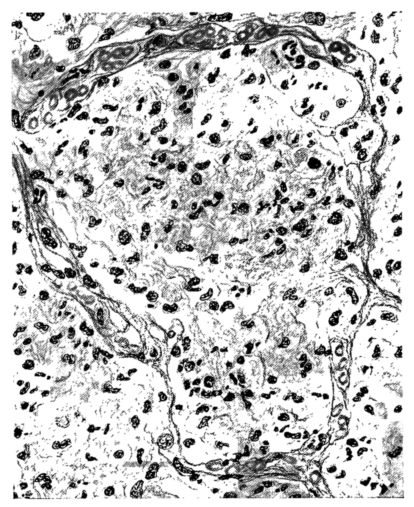

FIG. VII. AUTOPSY NO. 94. A NECROTIZING PROCESS LIKE THAT OF THE TRACHEA ILLUSTRATED IN FIGURE II. HERE IT IS SHOWN TO INVOLVE THE WALL OF THE BRONCHIOLE.

15There is considerable evidence to support the view that the disease spreads from bronchus to bronchus, and in keeping with this view, various stages in the inflammatory processes are more readily determined in these smaller structures than in the trachea. Furthermore, it must be emphasized that even the mildest and the most extreme of these stages are not infrequently encountered in the same lung. The earliest lesion is manifested by an increased homogeneity of the protoplasm of the epithelial lining of the bronchus. The cell protoplasm loses its normal granulation and the nucleus, somewhat darker than usual, becomes conspicuous on a red base (Fig. V). In the lumen of such a tube a serous exudate, perhaps mixed with mucus, is encountered, and there is some spreading apart of the surrounding muscular tissue with engorgement of the vessels. This picture merges gradually into one where the epithelium appears as a homogeneous, red-staining ribbon, devoid of nuclei, often exfoliated, in part at least, from the underlying submucosa (92). The change is traceable through the larger bronchi, even to the ducti alveolares, and not infrequently, bacteria, either as a diffuse, minute dotting or in the form of circumscribed, colony-like formations, are spread through the red, ribbon-like strand (Fig. XVI). With the exfoliation of the epithelial lining, the submucous vessels become more and more conspicuous and may bulge into the lumen of the tube (Fig. VI). That they actually weep into the lumen is proved by the presence of red blood cells in the exudate, now rich in mucus, broken-down nuclei, and desquamated cells. The necrotizing process may not extend deeper than the epithelial lining as is the status described above (140, 162), but it also frequently involves the underlying submucous and muscular layers, so that these lose their identity and stand out as homogeneous masses, in which fragmented nuclei and bacterial accumulations are prominent. Such deeper necrotizing areas may be focal (Fig. VII), or may involve the entire circumference of the tube (Fig. VIII). Occasionally, the epithelium, now dead and staining homogeneously, is lifted from the underlying submucosa in the form of a blister (66), and has very much the same appearance as the well known, early reaction which follows the application of croton oil to the rabbit’s ear. Where this occurs, the submucosa is less involved, as though the necrotizing agent had not penetrated to the same depth and the serous reaction beneath were actually a beneficent exudate. These blisters are in contrast with the deeper areas where the fibrinous mass, mixed with the dead tissue, forms an intensely staining ring or band, which extends through the bronchiolar wall even to the surrounding alveoli.